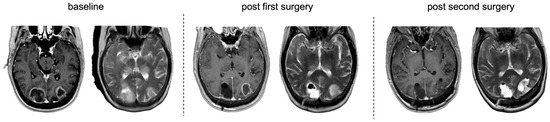

Prevalence and Clinicoradiopathological Characterization of H3 K27-Altered Diffuse Midline Gliomas in Adults—A Retrospective Observational Study

by Kristof Babarczy, Bence L. Radics, Lili Kiss, Alexandra Graczer, Bence Nagy, Sandor Dosa, Gyongyi Kelemen, Marton Balazsfi, Pal Barzo, Andras Voros, Peter Klivenyi and Levente Szalardy

Pathophysiology 2026, 33(1), 21; https://doi.org/10.3390/pathophysiology33010021 - 14 Mar 2026

Background/Objectives: Diffuse midline glioma (DMG), H3 K27M-altered, represents a rare group of gliomas arising in midline structures of the central nervous system. Historically regarded as a pediatric entity, it is now increasingly recognized in adults. Although its relative prevalence among all midline [...] Read more.

Background/Objectives: Diffuse midline glioma (DMG), H3 K27M-altered, represents a rare group of gliomas arising in midline structures of the central nervous system. Historically regarded as a pediatric entity, it is now increasingly recognized in adults. Although its relative prevalence among all midline diffuse gliomas and its clinical-radiological characteristics are well defined in children, these tumors remain less characterized in adults, and comparative evaluations with H3 K27 wildtype midline diffuse gliomas are limited. Methods: Consecutive adult patients with histopathologically confirmed diffuse glioma (WHO grade ≥ 2) diagnosed between 2016 and 2025 were retrospectively screened for midline tumor location, with systematic revision of imaging and pathology. For identified midline diffuse gliomas, comprehensive clinical, imaging, and immunohistochemical data were collected, and a detailed morphometric analysis was performed. H3 K27 alteration status was established immunohistochemically, with supplementary immunostaining when necessary. Descriptive and comparative analyses were conducted. Results: A total of 5% of the 541 adult diffuse gliomas were midline, and 23% of IDH wildtype midline gliomas were consistent with DMG, H3 K27-altered (all H3 K27M-mutant). The affected patients were significantly younger, and these tumors predominantly involved the thalamus and mesencephalon. Morphometric analyses revealed trends toward fewer high-grade features in H3 K27-altered tumors, with composite scores demonstrating significant discriminatory ability. The overall survival was not significantly different between groups but showed associations with ring-like enhancement as well as adjuvant and salvage therapies in the overall midline cohort. Conclusions: This study provides population-based prevalence estimates for DMG, H3 K27M-altered, and complements the limited literature with comparative clinical-radiological and morphometric data of potential prognostic relevance. Full article